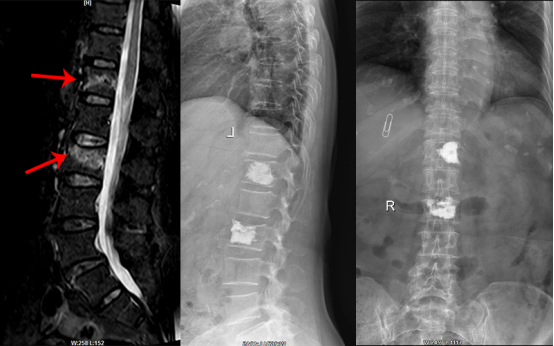

(4)微创固定技术治疗胸腰椎骨折

年轻人外伤后导致的胸腰椎骨折,通过小切口微创置钉固定,可复位骨折,重建脊柱稳定性,术后可早期活动,恢复正常日常生活。

图注:微创经皮椎弓根螺钉内固定,术中透视骨折复位满意。

(5)椎体成形术治疗老年骨质疏松性胸腰椎压缩骨折

是老年常见疾病,老年人骨质疏松,坐车颠簸、轻微外伤、甚至日常生活就可导致腰椎、胸椎压缩性骨折,翻身、起床、站立时胸腰背部疼痛难忍。通过PKP、PVP微创技术,局部麻醉或全麻下,皮肤切口约3mm,向骨折椎体内注入骨水泥,骨折椎体即刻稳定,疼痛解除,手术时间约30分钟,术后第二天就可下床活动,手术疗效好,恢复快,住院时间短。

图注:胸12、腰2椎体骨质疏松性压缩性骨折,行胸12、腰2锥体成形术。